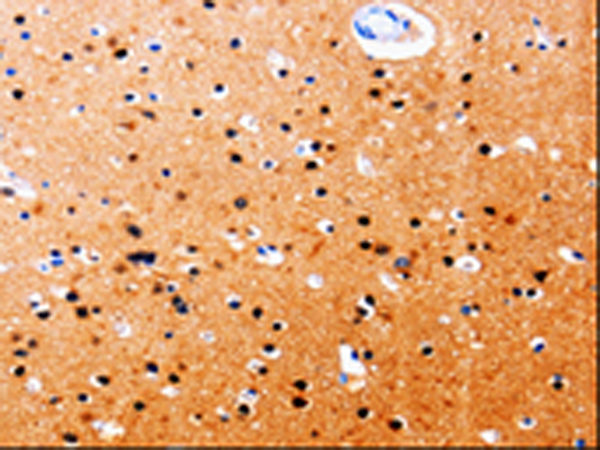

IHC positive control: |

Human brain and Human tonsil |

IHC Recommend dilution: |

25-50 |